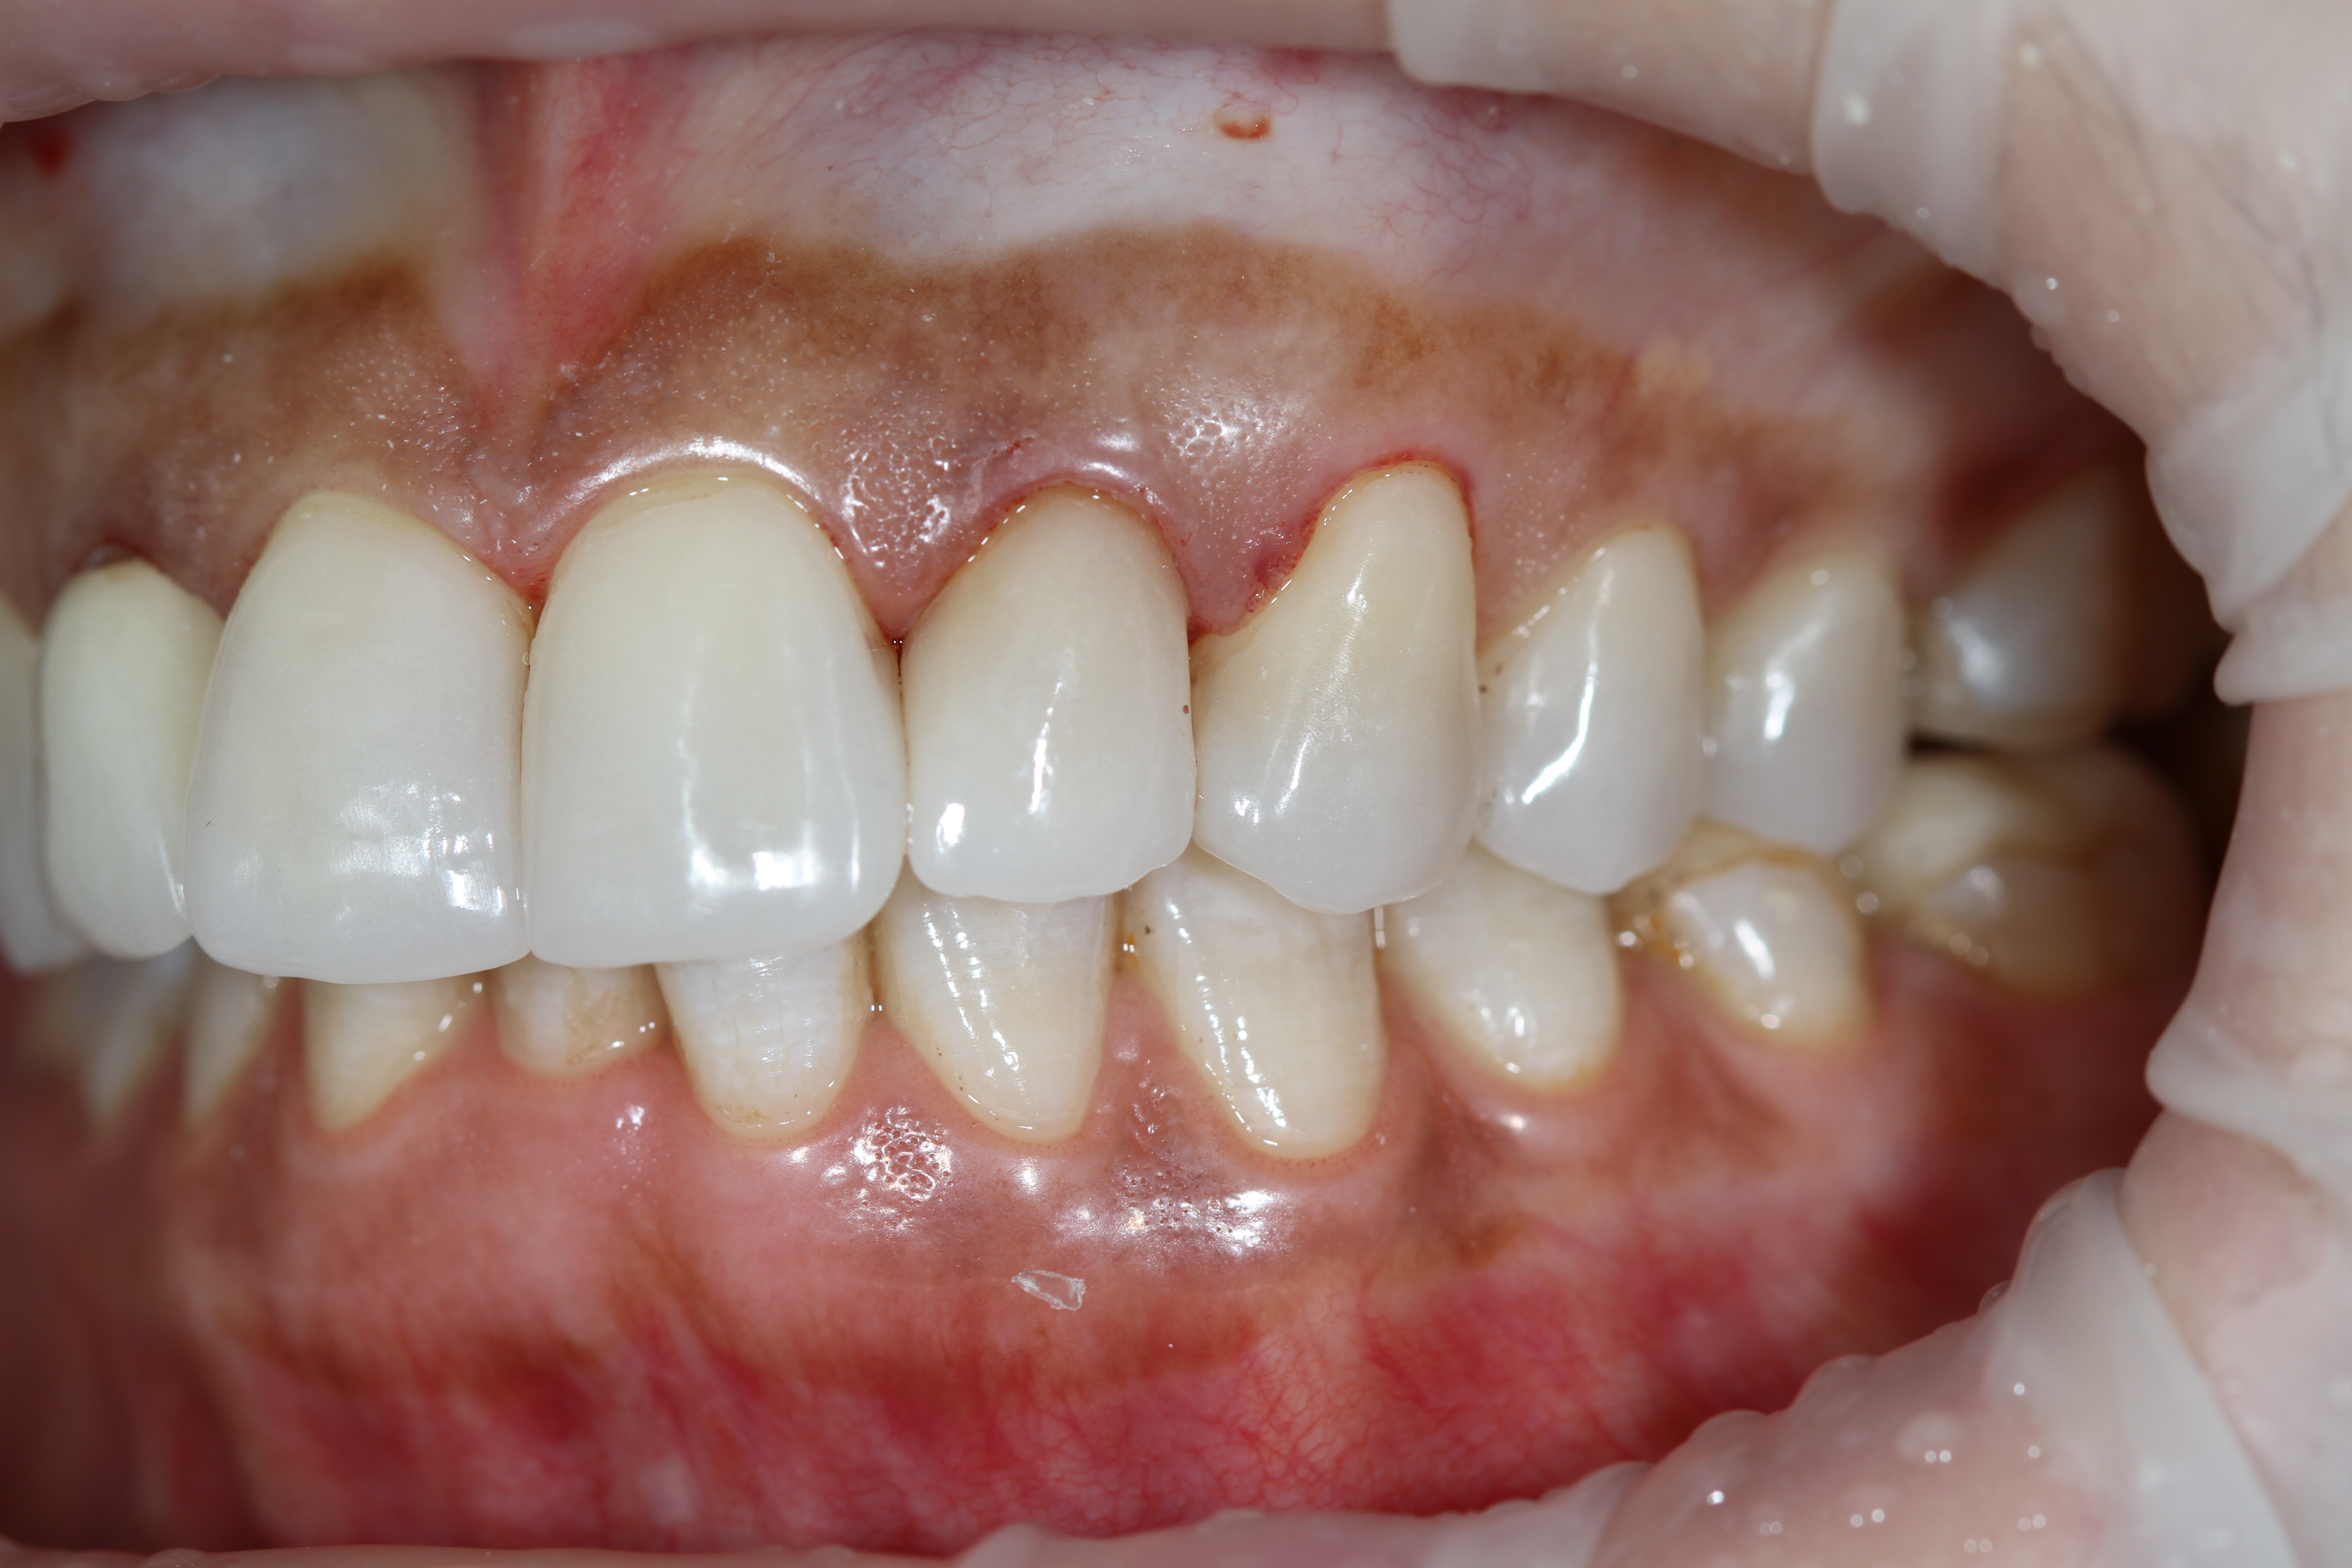

Снова виниры

Замена старых виниров темного цвета на более светлые по причине оголения шейки зуба.

Виниры цвета BLEACH

Установлены керамические виниры на верхнюю челюсть по эстетическим требованиям.